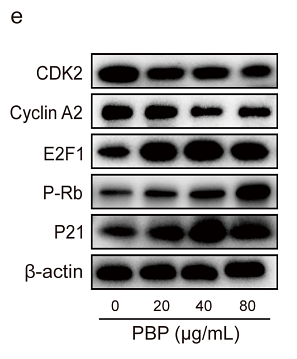

Elucidation of the anti-colon cancer mechanism of Phellinus baumii polyphenol by an integrative approach of network pharmacology and experimental verification

Author:

PMID: 37838121

期刊: International Journal Of Biological Macromolecules

应用: WB

反应种属: Human

发表时间: 2023 Oct